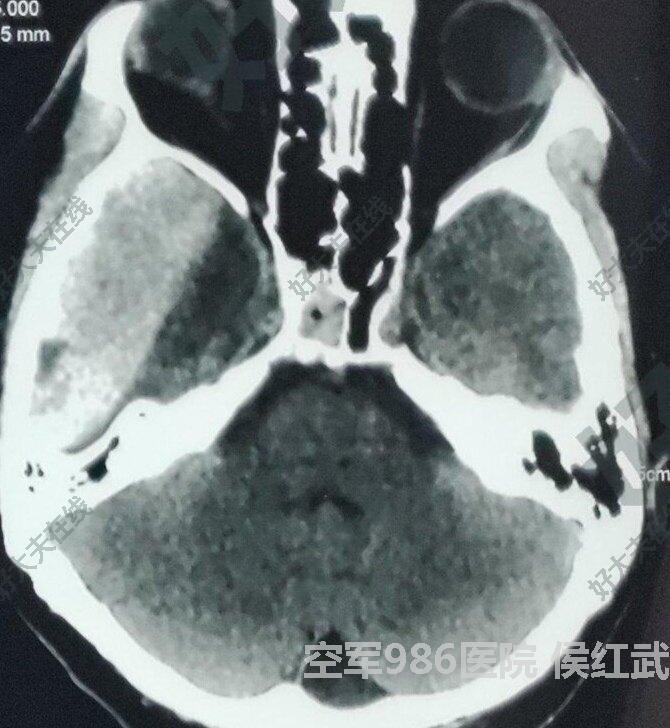

硬膜外血腫